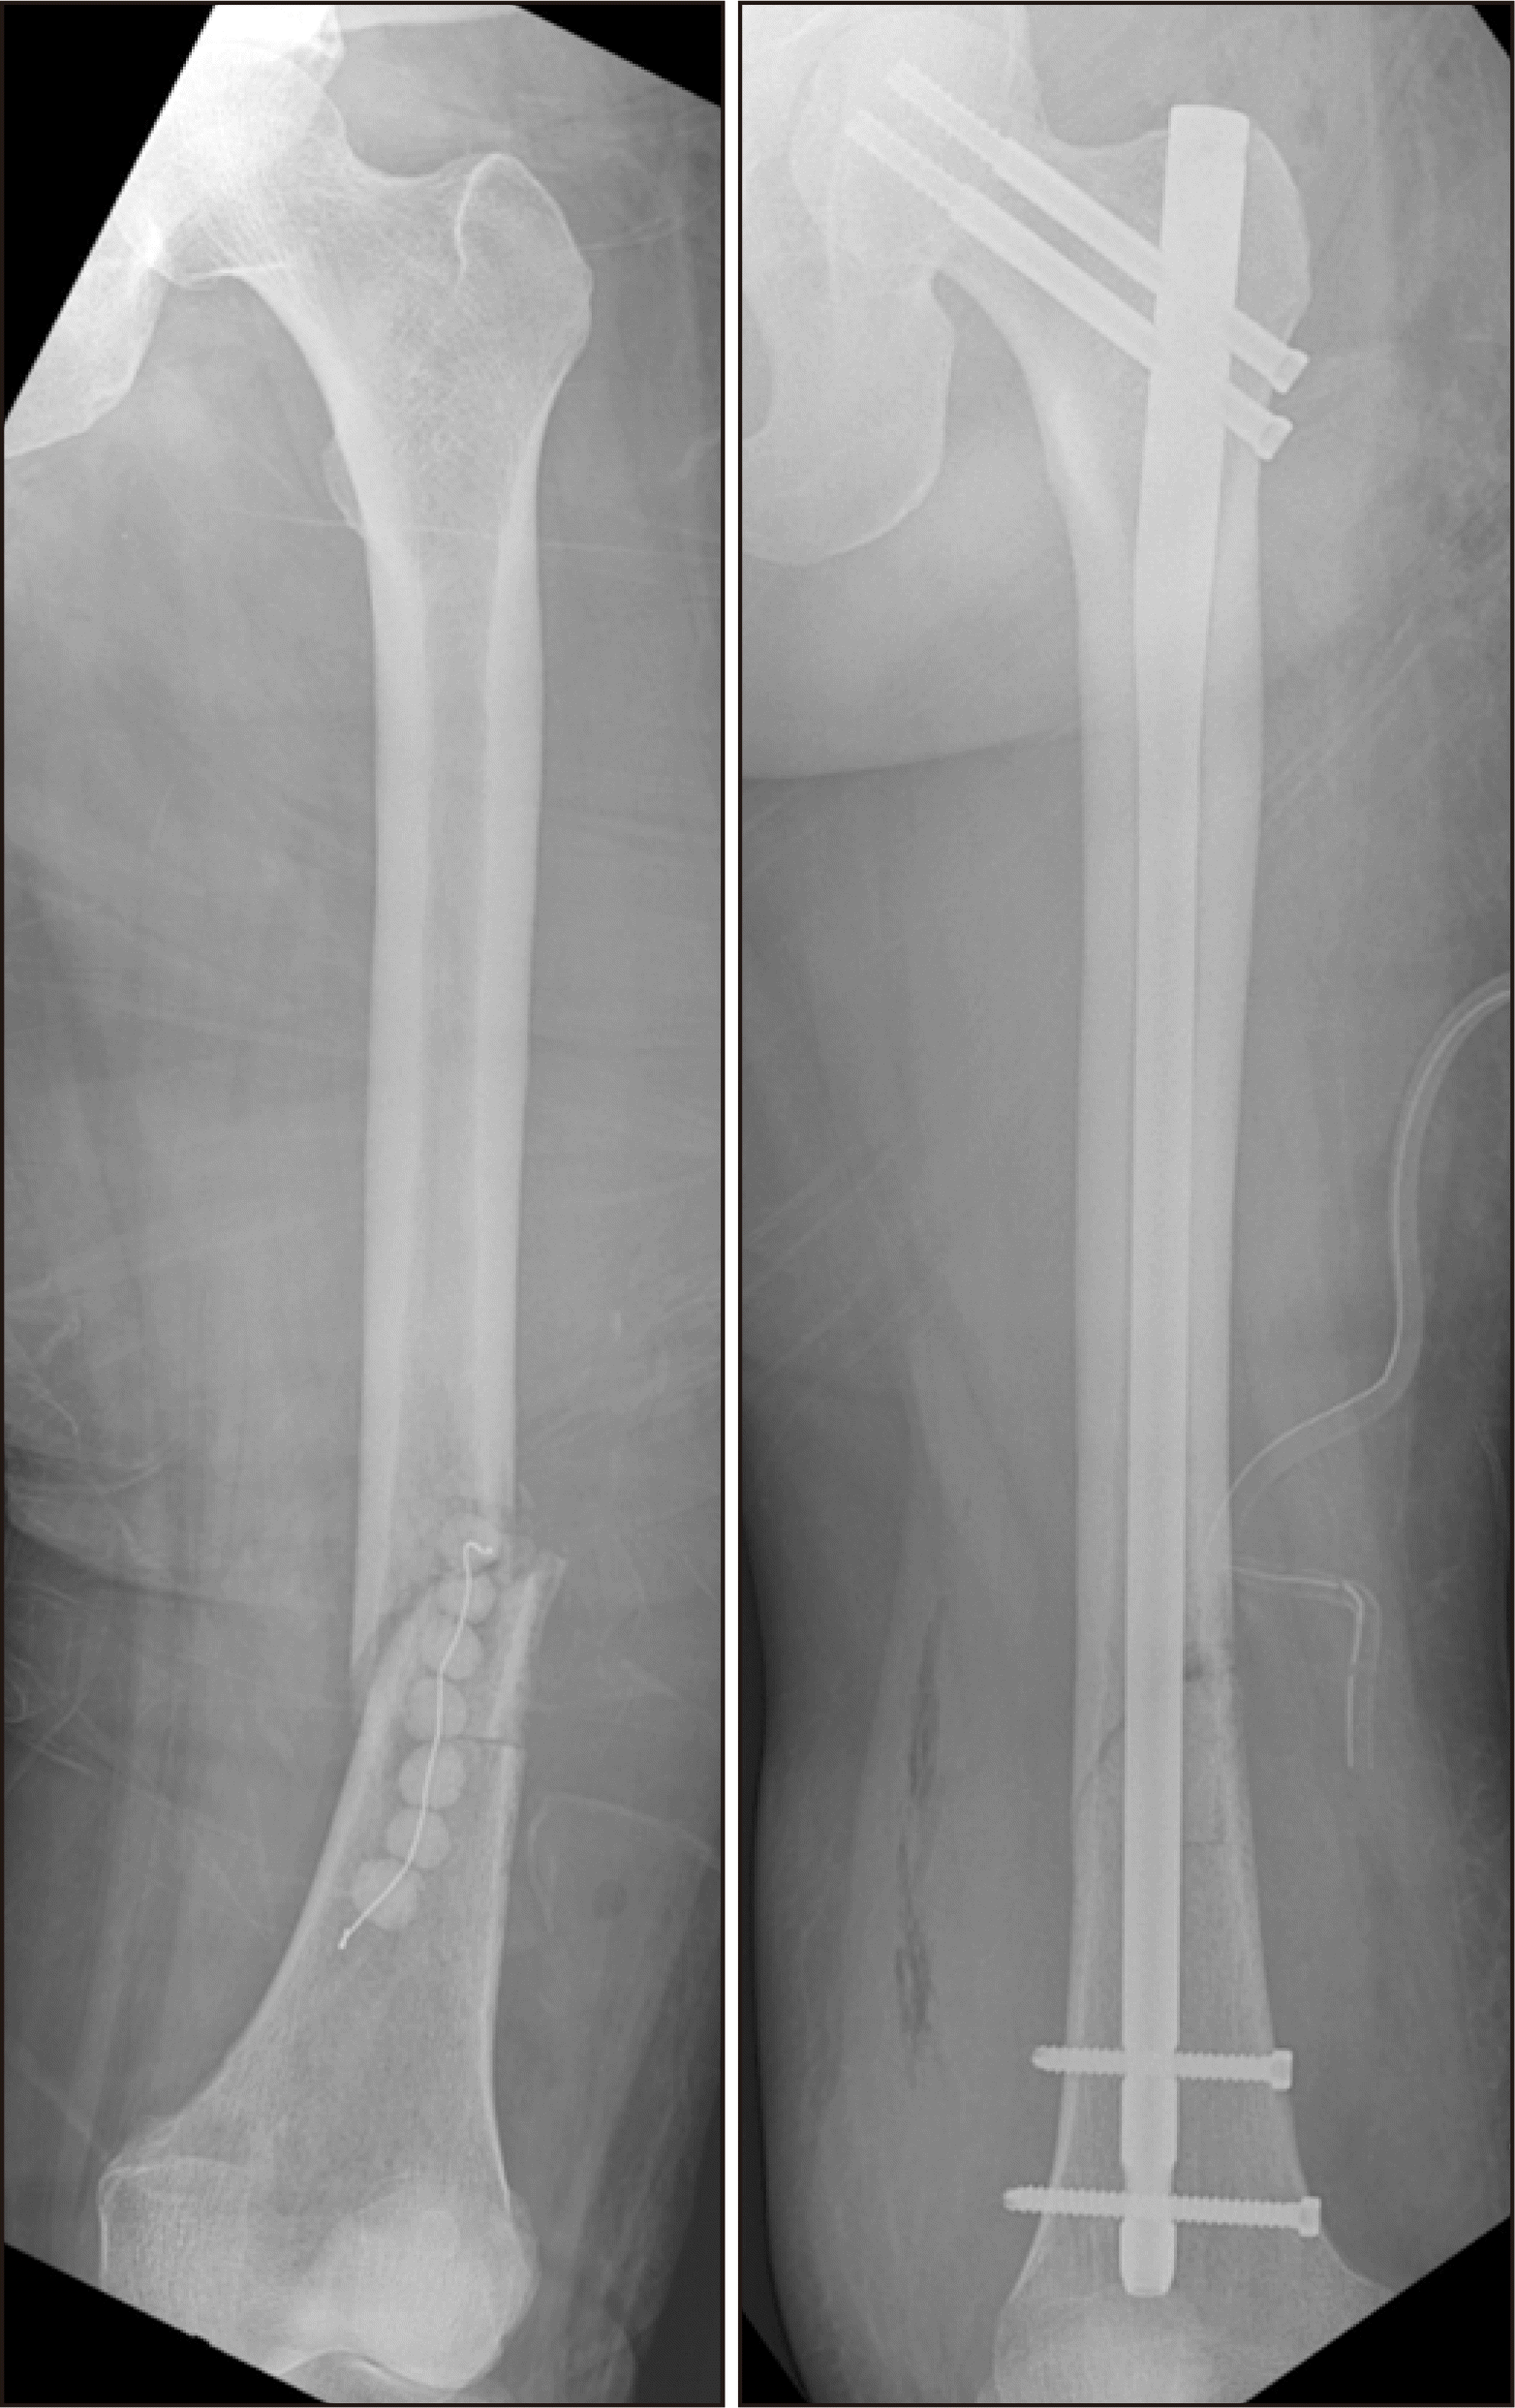

Figure 3

(A) The radiograph shows fracture of right femur shaft. There is the osteolytic lesion around fracture site. (B) In the enhanced magnetic resonance imaging, there are loculated fluid with thickened enhanced wall around fracture site in the muscles of right thigh.